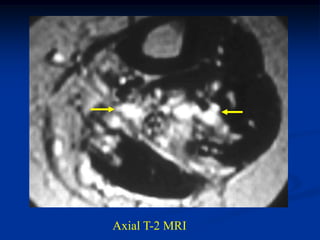

Case #1209

17 year male with

hemangioma in

quadriceps muscle

Axial T-2 MRI

Case #1209 17 yearmale with hemangioma in quadriceps muscle Axial T-2 MRI